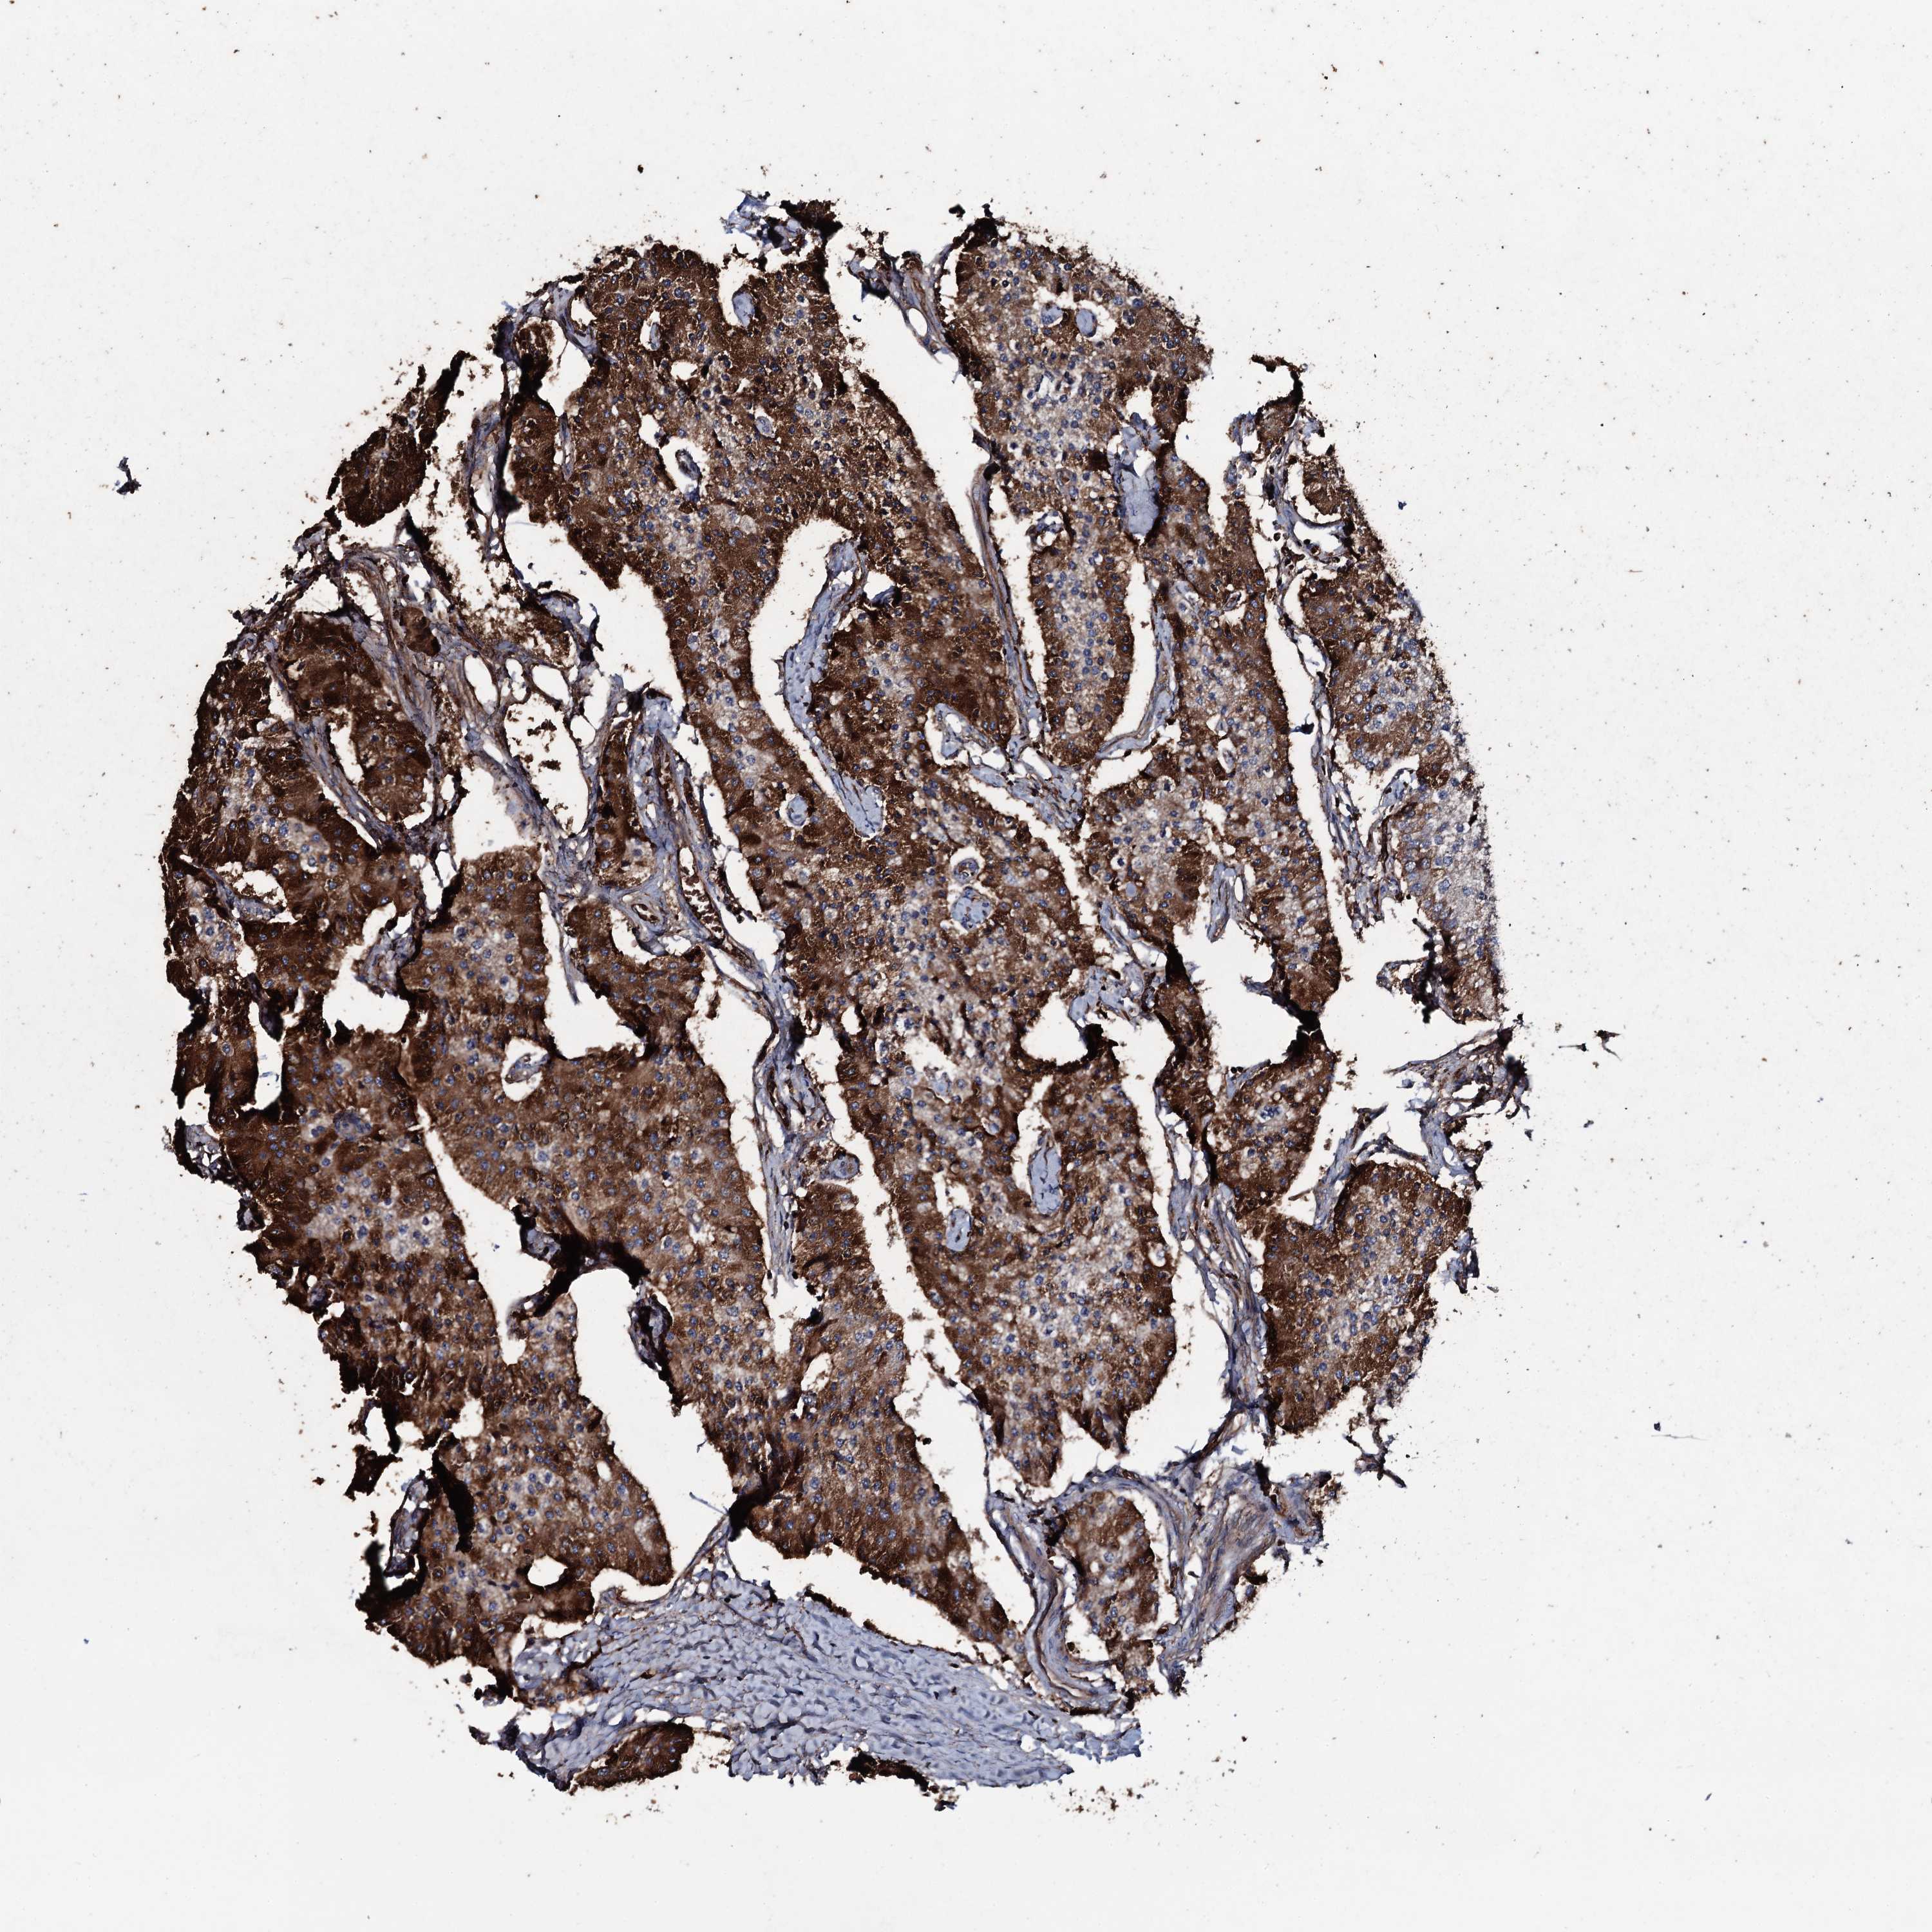

CARCINOID - Protein expressioni

A mouse-over function shows sample information and annotation data. Click on an image to view it in a full screen mode. Samples can be filtered based on level of antibody staining by selecting one or several of the following categories: high, medium, low and not detected. The assay and annotation is described here.

Each image is clickable and will lead to virtual microscopy that enables deeper exploration of all samples and also displays staining intensity scores, fraction scores and subcellular localization as well as patient and tissue information for each sample.

Antibody HPA041244

Staining

High

Medium

Low

Not detected

Intensity

Strong

Moderate

Weak

Negative

Quantity

>75%

75%-25%

<25%

None

Location

Nuclear

Cytoplasmic/membranous

Cytoplasmic/membranous,nuclear

Carcinoid, malignant, NOS

Carcinoma, NOS